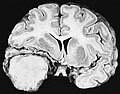

Gross/Radiology

- Extra-axial, intradural.

- Can be extradural - very rare.[10]

- Dural tail sign (DTS) on MRI.[11][12]

- +/-Hyperostosis.

- Associated with invasion into the skull in ~20% of cases.[15]